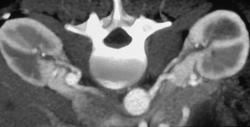

Transitional Cell Carcinoma of the Left Kidney